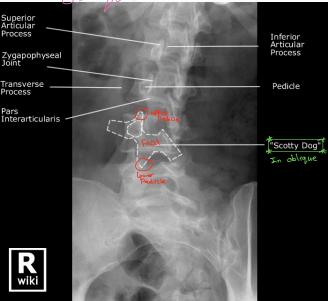

- Specialized Views:

- Oblique: 45° angle to see structures between foramen

Anatomical Structures Visible on Oblique View

- Superior Articular Process

- Zygapophyseal Joint

- Transverse Process

- Pars Interarticularis

- Inferior Articular Process

- Pedicle

“Scotty Dog” sign is visible on oblique radiographs